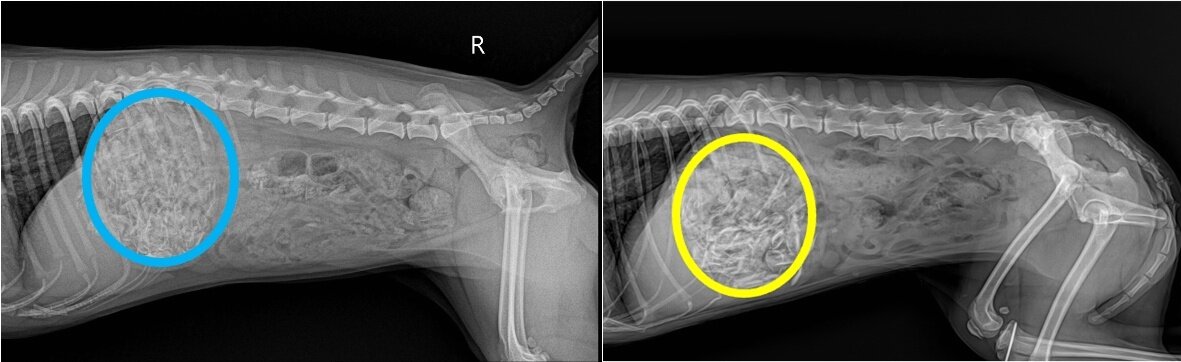

본문 이미지 - 닭뼈를 섭취한 두 마리 개의 방사선 사진(스카이동물메디컬센터 제공) ⓒ 뉴스1

닭뼈를 섭취한 두 마리 개의 방사선 사진(스카이동물메디컬센터 제공) ⓒ 뉴스1